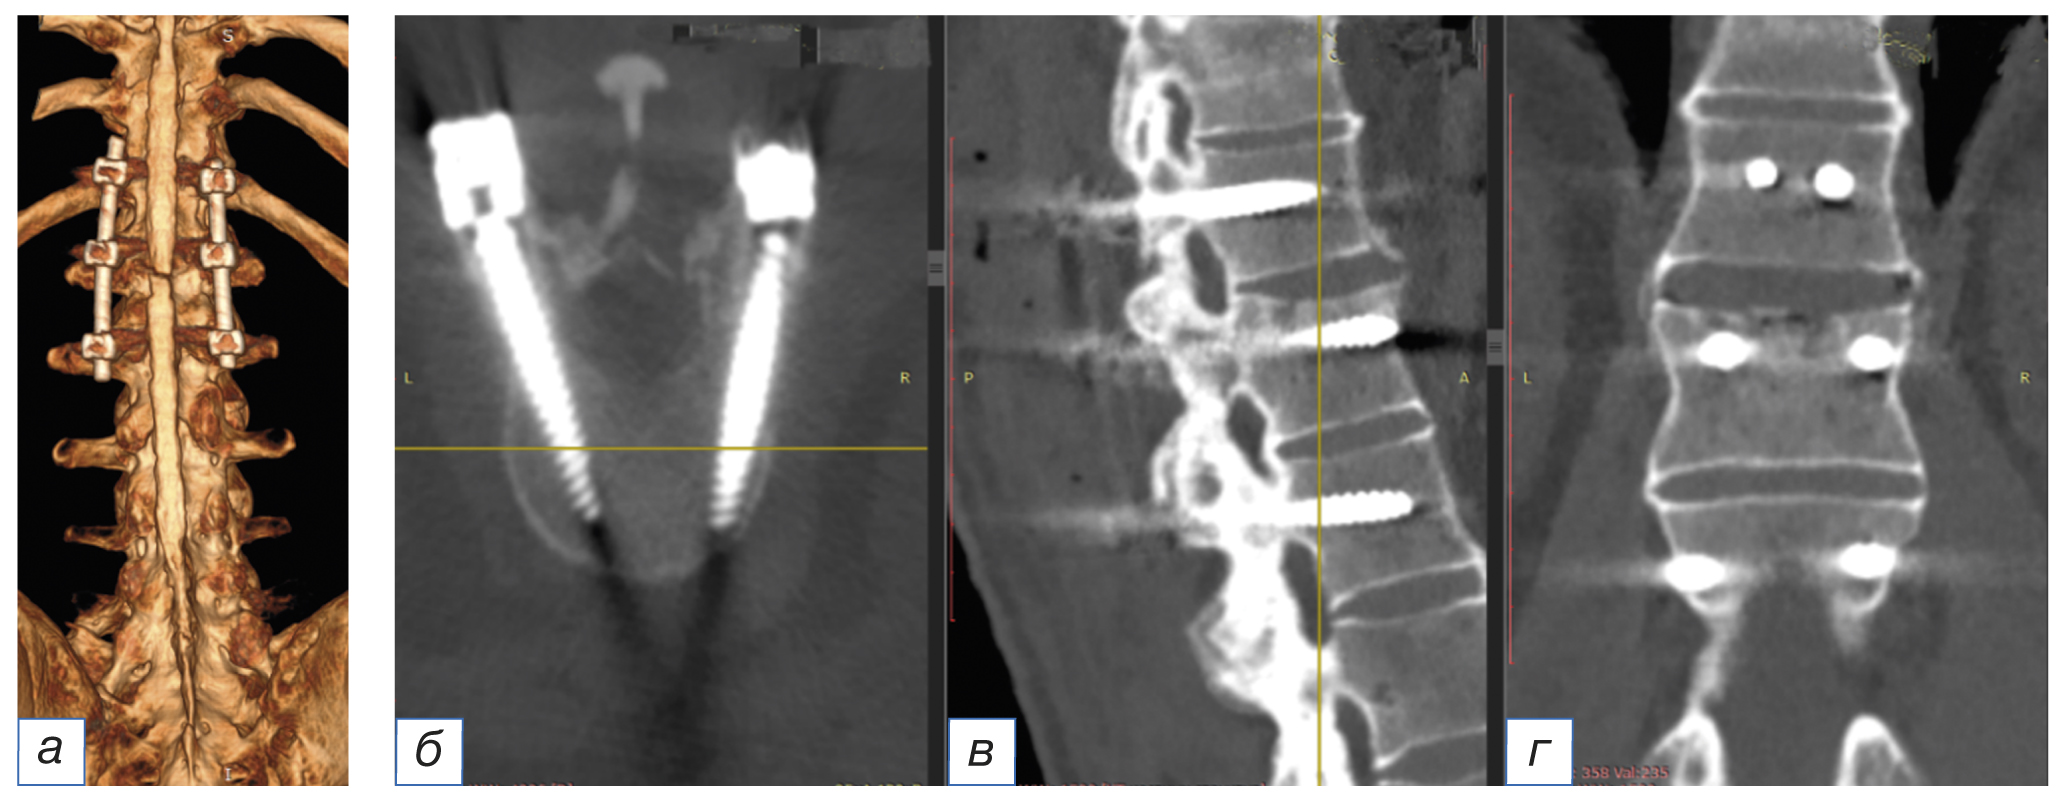

МСКТ-исследование грудопоясничного отдела позвоночника в положении пациента на спине. На томограммах позвонки имеют прямоугольную форму, обусловленную резорбцией углов; выявляется остеит передних углов тел позвонков; имеются вертикальные синдесмофиты наружных волокон фиброзного кольца, признаки диффузной остеопении. Выявлены разрыв передней продольной связки на уровне ThXII–LI позвонков, краевой перелом верхней замыкательной пластинки LI позвонка с продолжением линии перелома на суставные отростки ThXII–LI позвонков с формированием локальной деформации позвоночника на уровне перелома. Рентгенологически установлена нестабильность позвоночно-двигательного сегмента ThXII–LI (перелом трёх колонн) с формированием локальной деформации позвоночника на уровне перелома (рис. 1).

Рис. 1. Предоперационная визуализация перелома с помощью мультиспиральной компьютерной томографии: а — 3D-реконструкция грудопоясничного отдела позвоночника; б — аксиальный, сагиттальный, фронтальный срез на уровне ThXII–LI (стрелкой указана линия перелома).